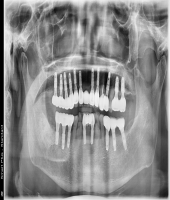

| ● 진료과목 : [임플란트] 10년의 변화

| ● 내용 : 10년간 다양한 임플란트를 식립한 케이스입니다. |